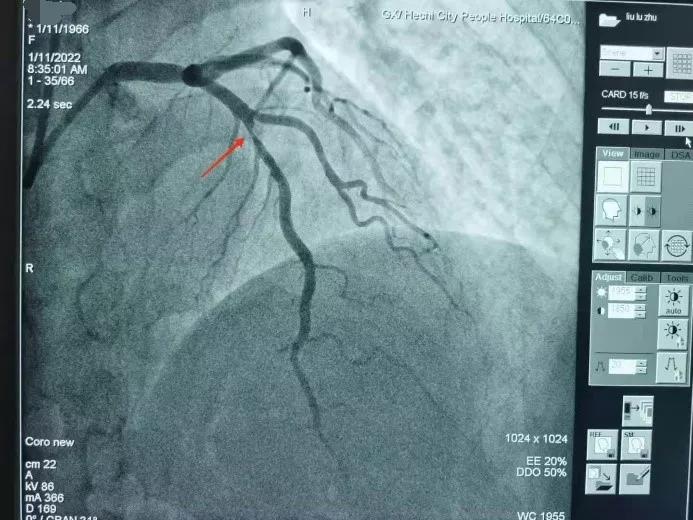

近日,50岁的黄女士因胸闷、气促、头晕等症状逐渐加重,随即到河池市人民医院心血管内科一病区诊治。经检查发现,其冠状动脉血管前降支中段堵塞已达到90%,需行支架植入术解除狭窄病变。为了使患者获得最佳治疗效果,唐秀革院长和莫昌干主任反复讨论手术方案,认为患者血管病变特点适合行生物可降解支架植入术。

术前造影

在介入室医护人员的配合下,唐秀革院长和莫昌干主任凭借丰富的手术经验和娴熟的技术,将一枚生物可降解支架精准地植入患者病变血管内,造影显示狭窄的血管即刻恢复血流,手术非常顺利,整个手术过程用时仅50分钟。术后,患者恢复良好,胸痛症状明显改善,患者及家属对心血管内科医师们精湛的医术给予高度评价。